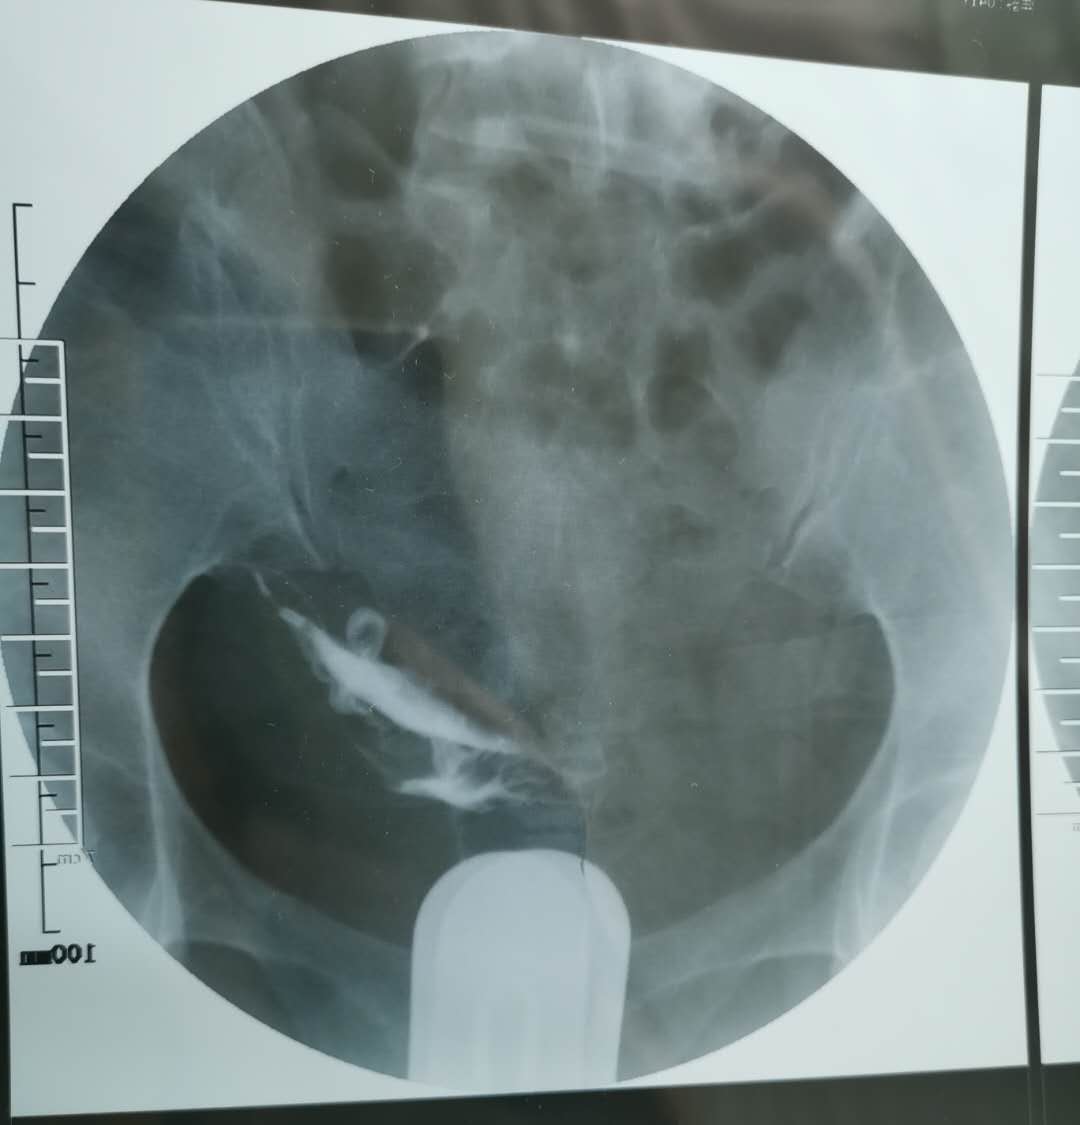

我这个是做了输卵管介入手术,请问输卵管是通了

做完输卵管造影第六天了小腹还是感觉沉甸甸的如

可以热敷腹部,如果有发热,腹痛加剧,白带量多,有异味,随时就医